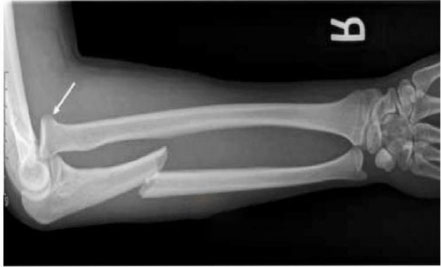

Soru: Düşme nedeniyle acil servise getirilen hastanın grafisinde ulna cisminde kırık ve radius başı çıkığı saptanmıştır (Görüntü tarif edilmiştir).

Aşağıdakilerden hangisi bu hastada tespit edilebilecek en olası kırık türüdür?